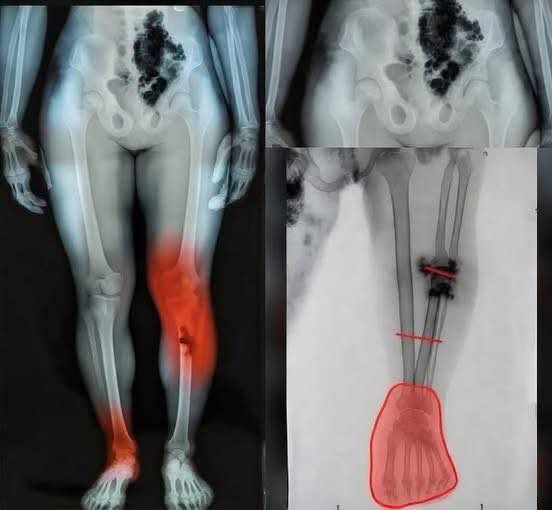

Experts emphasize that the human body can respond in complex ways after illness, especially when the immune system has been heavily activated. In some cases, inflammation can linger or affect areas that weren’t initially involved. That doesn’t necessarily mean something dangerous is happening, but it does highlight how much researchers are still learning about long-term effects.

At the same time, doctors are urging people not to panic or jump to conclusions based on isolated images or claims online. Not every symptom is directly linked, and not every experience follows the same path. The key message remains clear: if something feels unusual or persistent, it’s important to get it checked rather than relying on speculation.